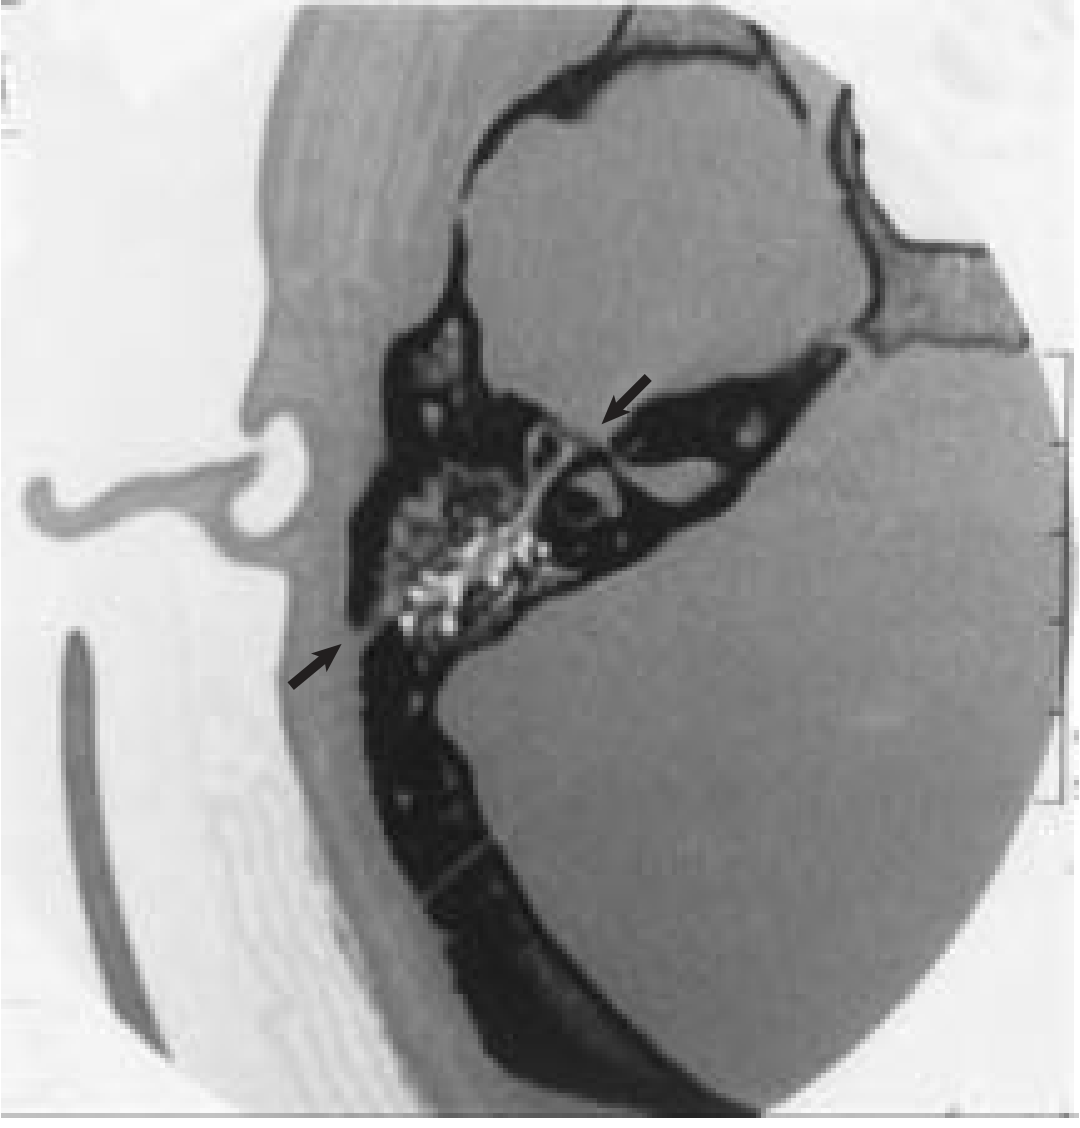

CT scan of temporal bone showing longitudinally-oriented fracture line (arrows) sparing the otic capsule

CT Temporal Bone — Otic capsule-sparing fracture (for comparison). In transverse fractures the fracture line crosses the otic capsule. — Cummings Otolaryngology